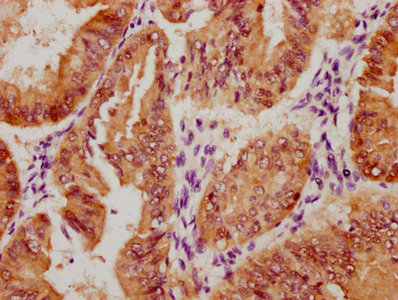

Immunohistochemistry of paraffin-embedded human lung cancer using CSB-PA010418PA10nphHU at dilution of 1:100